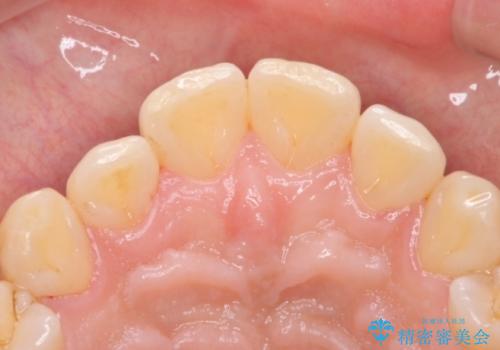

PMTCによる着色除去

- 着色が気になるとのことで来院された。

着色だけでなく、歯石やバイオフィルムの除去、ハイドロキシアパタイト配合のトリートメントで仕上げ磨きまで行います。